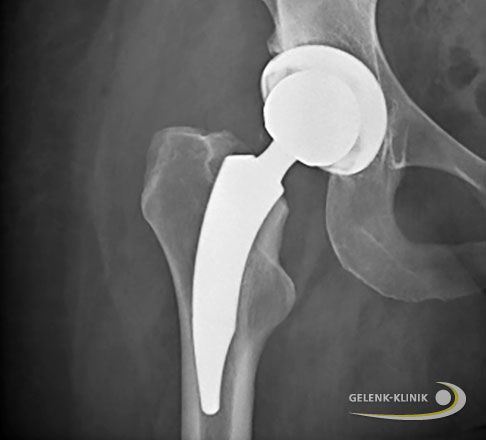

Einsatz einer Hüftprothese bei fortgeschrittener Hüftarthrose

Sind die arthrotischen Verschleißerscheinungen im Hüftgelenk zu weit fortgeschritten und konservative Therapien erzielen keine Linderung der Schmerzen, bespricht der Arzt mit dem Patienten die Notwendigkeit für ein künstliches Hüftgelenk.

Ob das komplette Gelenk oder nur Teile davon durch eine Prothese ersetzt werden, hängt vom vorliegenden Schaden ab: Ist die Hüftpfanne noch unversehrt, der Oberschenkelkopf dagegen bereits degeneriert, reicht eine Hüft-Teilprothese aus. Sind beide Gelenkanteile von Verschleiß betroffen, zieht der Orthopäde eine Hüft-Totalendoprothese (Hüft-TEP) in Betracht.

Bei bereits bestehender Arthrose im Hüftgelenk besteht die Möglichkeit, den Patienten mit einer Hüft-Teilprothese oder einer Hüft-Totalendoprothese zu Schmerzfreiheit zu verhelfen. Je nachdem, ob nur eine oder beide Gelenkflächen von Arthrose betroffen sind, wird entsprechend der operative Eingriff geplant. Der Einsatz einer Hüftprothese hat unserer Erfahrung nach für die Patienten weitreichende positive Effekte auf ihre wiedererlangte Beweglichkeit und die gesteigerte Lebensqualität.